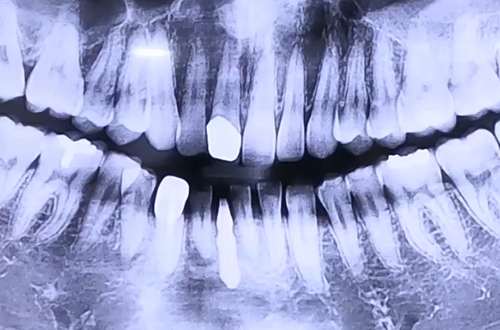

AFTER

환자분께서 이 좁아진 공간에 임플란트 하나로 빠른 치료를 요청하셨기 때문에

몸통과 머리 부분이 하나로 되어 가늘게 제작 가능한 원바디 임플란트를 결정하였습니다.

좁아진 앞니 자리에는 원바디임플란트를 식립하고, 윗니 앞니와 아랫니 송곳니는

예쁜 보철을 빠르게 먼저 완성해 드렸으며 임플란트가 굳기까지 4개월동안

임시치아를 사용하신 뒤 최근 최종 보철까지 완성하셨습니다. ^^